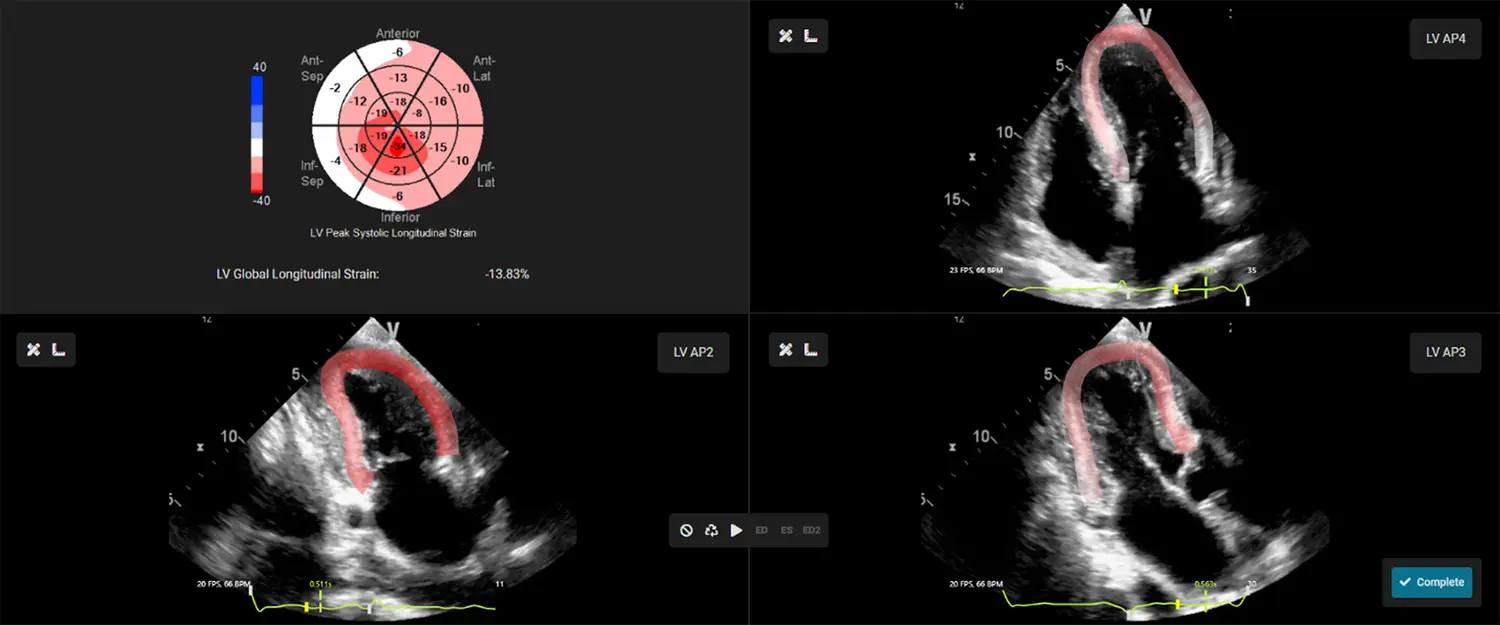

EchoInsight® Zero Footprint with AutoAssist™ is an offline, vendor-neutral, zero-footprint, zero-click echo analysis platform that runs from a single server.

Leverage EchoInsight® ZF to integrate advanced echo analysis into your routine practice.